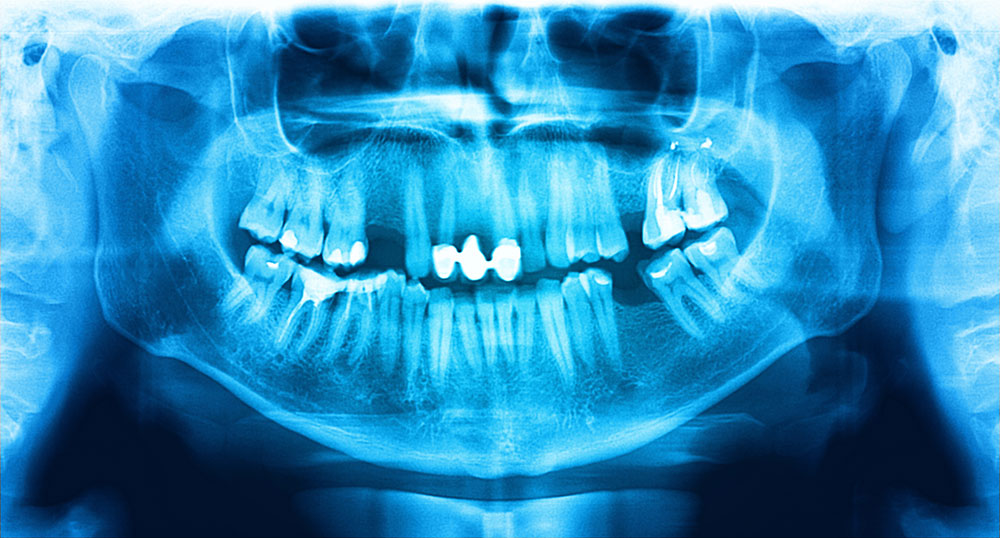

根管治療において精密な診断が重要だと考えているため、デジタルレントゲンやマイクロスコープを使用して、歯の内部構造を詳細に確認しています。根管の曲がりや分岐など、目に見えない部分まで精密に評価することで、治療計画をより精密に立てることができます。

まずは、詳細な診察とデジタルレントゲンによる撮影をおこない、感染の程度や根管の状態を精密に把握します。この段階で、治療計画を立て、患者さまに治療内容を丁寧に説明します。